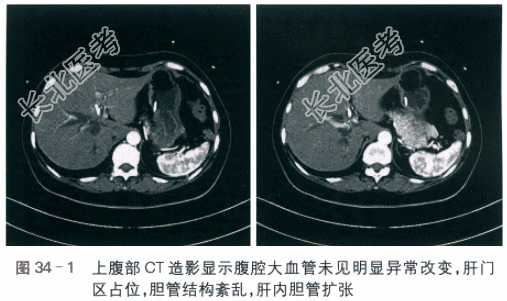

- [材料题] 现病史 患者,女性,54岁,因“1个月前无明显诱因下出现皮肤巩膜黄染”就诊。患者无恶心呕吐,无寒战发热,自觉无明显腹痛,无腹泻,大便成型、色变浅,小便色渐黄,遂前往外院就诊。查磁共振胰胆管造影(MRCP)提示:胆囊体积较大,形态不规则,肝内胆管扩张,管径粗细不均匀,最宽约7mm,左右肝管汇合处管径变细,腔内未见明显充盈缺损灶。肝外胆管未见明显扩张,腔内未见明显充盈缺损灶。经护肝等保守治疗后症状未明显改善,遂1周前于外院行逆行性胆胰管造影(ERCP),术中造影提示肝总管至左肝管开口处见明显狭窄,肝外胆管未见明显扩张,未见明显充盈缺损,考虑Ⅳ型胆管癌,放置内支架并放置鼻胆管引流。术后黄疸渐减轻,总胆红素浓度降至64.5μmol/L,结合胆红素浓度降至34μmol/L,间接胆红素浓度30.5μmol/L,为求进一步诊疗来本院就诊,收入病房。2.既往史:患者既往体健,无特殊疾病史,无食物药物过敏史,无手术外伤史。3.体格检查:患者神清,精神可。视诊:皮肤巩膜黄染;全腹平坦,腹壁静脉未见,腹式呼吸存在,胃肠蠕动波不可见。触诊:腹软,无压痛,无反跳痛,未及腹块,Murphy征(-)。叩诊:无移动性浊音,肝区轻度叩痛,无肾区叩击痛。听诊:肠鸣音可及,无亢进。Courvoisier征(+)。4.实验室和影像学检查(1)肝功能检测:TB浓度为57.2μmol/L;DB浓度为23.7μmol/L;Alb水平为35g/L。(2)肿瘤指标:CA-125水平为11.7IU/ml;CA-199水平为125.2IU/ml;癌胚抗原(CEA)水平为2.24mg/ml;甲胎蛋白(AFP)水平为3.4ng/ml。(3)外院MRCP报告:胆囊体积较大,形态不规则,走行迂曲,胆囊腔内未见明显充盈缺损灶。胆囊管未见明显扩张,腔内未见明显充盈缺损。肝内胆管扩张,管径粗细不均匀,最宽约7mm,左右肝管汇合处管径变细,腔内未见明显充盈缺损灶。肝外胆管未见明显扩张,腔内未见明显充盈缺损灶。胰管走行迂曲,粗细尚均匀,未见明显扩张。(4)外院ERCP术中所见:肝总管至左肝管开口处见明显狭窄,肝外胆管未见明显扩张,未见明显充盈缺损。胆囊未显影,胰管未显影,考虑Ⅳ型胆管癌。(5)上腹部CT血管造影(CTA):腹腔大血管未见明显异常改变,肝门区占位,胆管结构紊乱,肝内胆管扩张(见图34-1)。